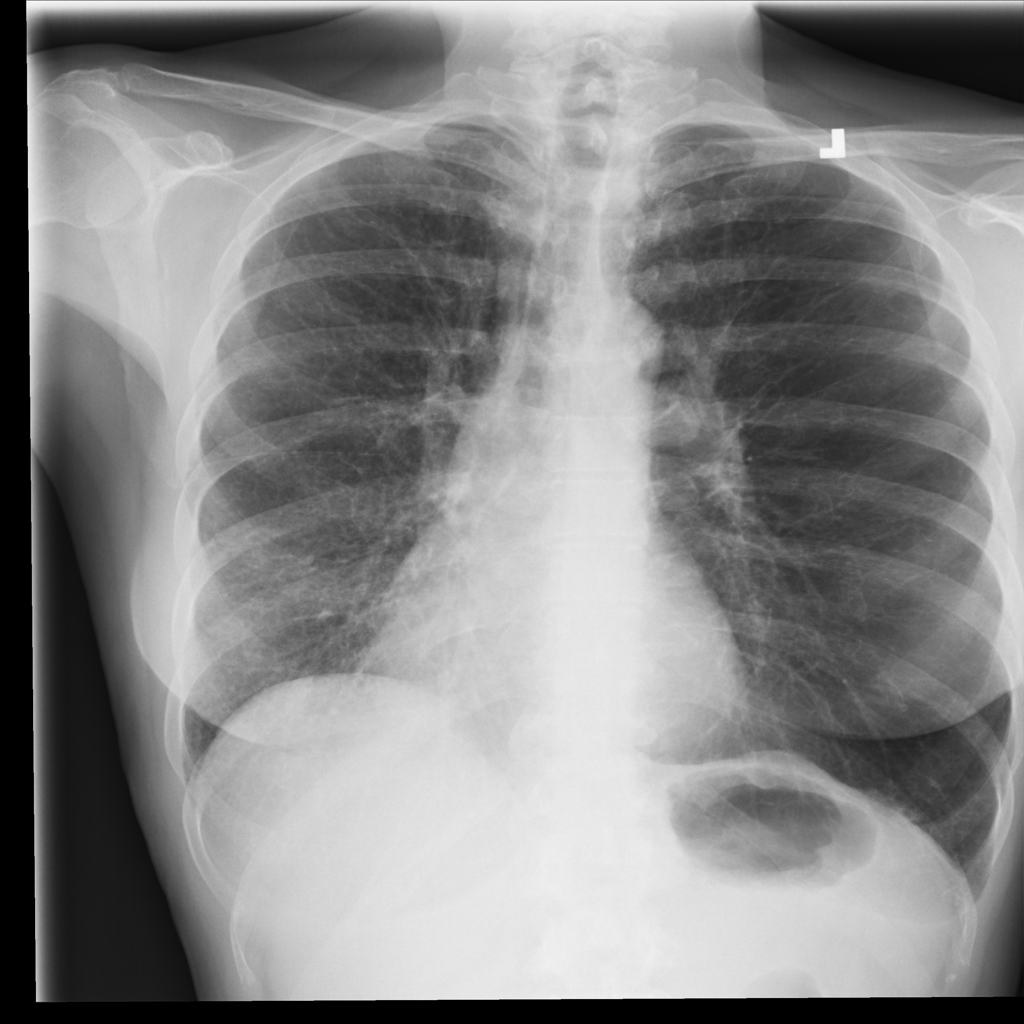

PAT-C77C · IMG-003Fibrosis

PAT-C77C · IMG-003

PA